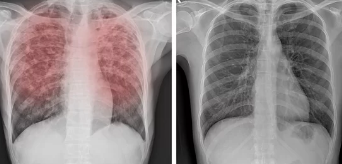

3. 폐 결절, 어떻게 진단하나요? 조기 발견이 중요!

폐 결절은 건강검진 시 흉부 X-ray 검사나 저선량 흉부 CT 검사를 통해 우연히 발견되는 경우가 많습니다.

결절 크기, 모양, 위치, 석회화 여부 등을 종합적으로 고려하여 악성 여부를 판단합니다.

필요한 경우에는 조직 검사를 시행하여 정확한 진단을 내립니다.

- 정기적인 검진: 흉부 X-ray 검사나 저선량 흉부 CT 검사를 통해 폐 결절을 조기에 발견하고 치료하는 것이 중요합니다.